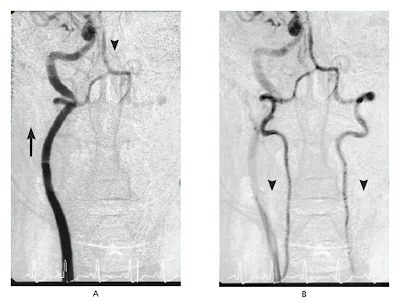

La angio-TC mostró embolias pulmonares no obstructivas en las arterias pulmonares principales. Múltiples pequeños defectos de relleno dentro de las arterias segmentarias del lóbulo superior izquierdo y lóbulo superior derecho. El catéter pericárdico fue removido 48 horas más tarde, una vez que el débito bajo a cero. Se comenzó con warfarina y cuando los valores de RIN fueron adecuados se interrumpió la heparina.

Tres semanas más tarde, el paciente notó un dolor pleurítico en el lado derecho del tórax por lo que consultó nuevamente al departamento de emergencias del hospital. El RIN era de 1,6. Se le realizó una nueva angio-TC que mostró resolución del derrame pleural, y derrame pericárdico loculado, adyacente al lado derecho del corazón. No había nuevos émbolos pulmonares. Un ecocardiograma transtorácico reveló crecimiento del derrame pericárdico con evidencias ecocardiográficas de taponamiento cardíaco. Se planificó una biopsia y realización de una ventana pericárdica.

Un ecocardiograma transesofágico que fue llevado a cabo antes del procedimiento, reveló un derrame pericárdico tabicado y lobulado, una masa ecodensa alrededor de la aurícula derecha, con comunicación con la cavidad de la aurícula derecha. El Doppler colo después de la administración de material de contraste reveló una comunicación entre la aurícula derecha y el espacio pericárdico (Figura 2 ). El espacio pericárdico medía 4 cm por 9 cm y el defecto en la aurícula derecha medía 5 mm . La realización de una ventana pericárdica fue abortada.